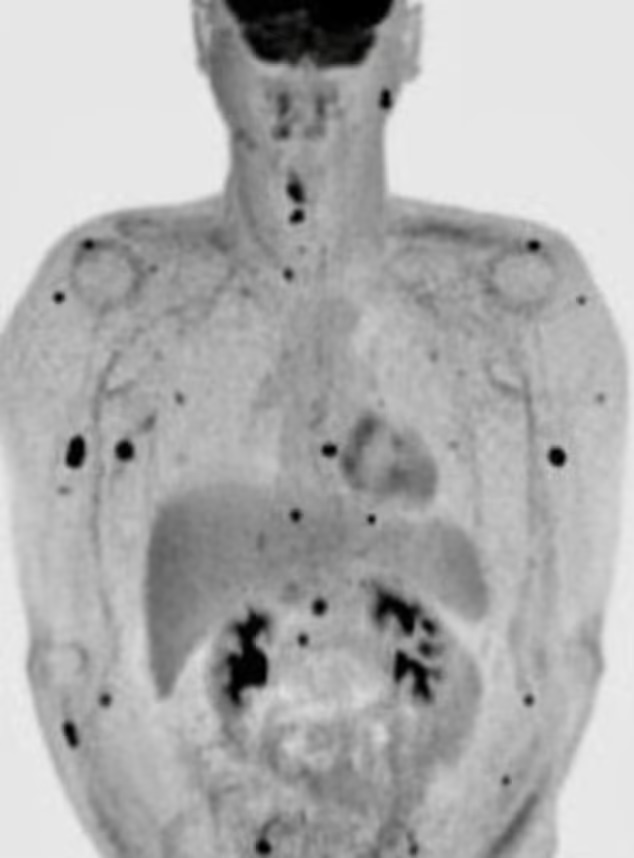

Days after having his lymph nodes removed in a ten-hour procedure known as the bilateral neck dissection, Smithson spotted a new growth just behind his ear, prompting him to undergo a PET scan.

Further testing revealed that cancer had already spread to different parts of his body including most of his organs and that his condition was terminal.